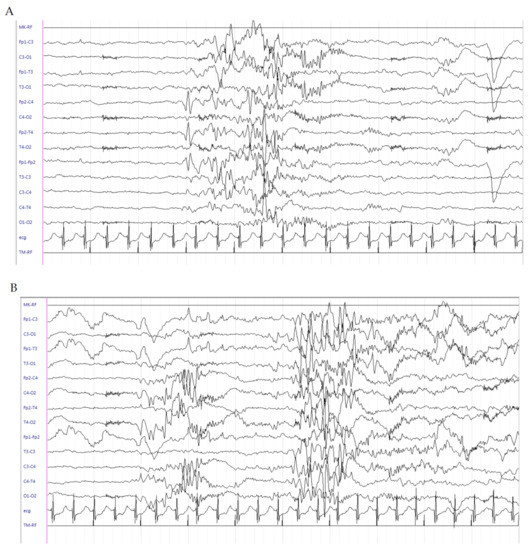

This is a female patient born at 404/7 weeks of GA from an unremarkable pregnancy by spontaneous vaginal delivery. Her birth weight was 2100 g (<3rd percentile). No perinatal distress was referred, and she was breastfed. On the 3rd day of life, the patient presented with focal seizures mainly characterized by lateralized tonic posturing and flushing, followed by clonic jerks at the same side, later shifting to the contralateral side, associated with perioral cyanosis and sweating lasting almost 30–50 sec, recurring many times a day. Family history was negative for epilepsy and other neuropsychiatric disorders. On the 5th day of life, due to persistence of clinical seizures, lethargy and poor feeding, the child was admitted to the NICU of our hospital. Seizures phenomenology appeared to be heterogeneous with some episodes characterized by generalized hypertonia, numbness and staring; others by focal clonic jerks of the right side; and still others by generalized clonic jerks. The interictal EEG failed to show epileptic discharges. In contrast, the ictal EEG showed focal slowing in the left central region, followed by appearance of medium–high-voltage, rapid, spiky activity in the left central region, suddenly generalizing. High-voltage and medium-voltage delta activity mainly in the right central region was evident at the end of the seizure (Figure 2A–D). Interictal EEG recording shows brief medium-voltage spike–slow wave discharges either in the left or right central regions, mostly asynchronous (Figure 2E,F). The patient underwent LEV 40 mg/kg administered as a bolus, with transient benefit. Oral pyridoxine (100 mg) was administered without benefits. Continuous IV midazolam infusion was kept on and uptitrated to 6 μg/kg/min, with seizure rate reduction but persistence of the interictal discharges consisting of prevalent isolated events of brief sharp wave–slow wave complexes turned over to the frontal lobe (Figure 2G). Extensive routine and metabolic investigations assessed according to previously described methods were unremarkable [6]. Cranial Ultrasound Scan (cUS) and brain MRI scans were normal. For this reason, next-generation sequencing analysis for genetic epilepsies was performed on peripheral leukocyte blood samples of the patient and both her parents, once written informed consent was obtained. On the 9th day of life, a sleeping EEG showed the presence of electroclinical episodes with slight motor and dysautonomic phenomenology. The interictal EEG showed focal discharges apparently shifting from one side to the other, sometimes interspersed with brief tracts of diffuse flattening. LEV was increased to 10 mg/kg/dose three times daily without benefit. PB 20 mg/kg was administered as a bolus with a transient reduction of seizures, but with subsequent relapse and persistence of interictal discharges. On the 10th day of life, therapy with hydrocortisone (5 mg/kg) was started, with seizures disappearing after 24 h. The EEG showed gradual disappearance of the abnormal discharges with gradual onset of physiologic tracé alternant of the newborn (Figure 2H). A gradual withdrawal of midazolam was performed. On the 21st day of life, hydrocortisone was gradually decreased and subsequently withdrawn on the 29th day of life. At this time, neurological examination showed axial hypotonia and poor spontaneous motility, which were markedly improved at the time of the patient’s discharge at 1 month of age. At the 3-month follow-up, the neurological examination showed persistent slight axial hypotonia and mild functional hand asymmetry at the right side. The patient continued LEV (150 mg/day) and she was seizure-free. Next-generation sequencing revealed the presence of a de novo heterozygous mutation in the KCNQ2 gene (c.2555delC (p.Pro852Argfs*78)). At the 6-month follow-up, the patient was seizure-free and the EEG showed high-voltage theta frequencies with sporadic rapid activity in the frontal regions and continued LEV therapy (150 mg/day). Neurological examination was unchanged.

Figure 2.

Electroencephalogram (EEG) of patient 2. (A–D) Ictal EEG shows focal slowing in the left central region, followed by appearance of medium–high-voltage, rapid, spiky activity in the left central region, suddenly generalizing. High-voltage and medium-voltage delta activity mainly in the right central region is evident at the end of the seizure. (E,F): Interictal EEG recording shows brief medium-voltage spike–slow wave discharges in either the left or right central regions, mostly asynchronous. (G): Interictal discharges consisting of prevalent isolated events of brief sharp wave–slow wave complexes turned over to the frontal lobe (left > right). (H): Gradual onset of tracé alternant of the newborn.